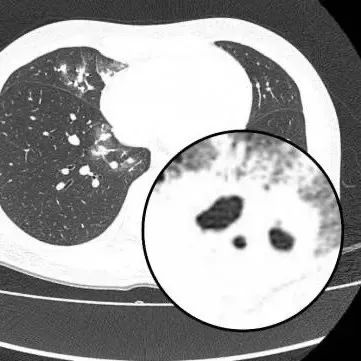

胸部CT显示其双肺多发感染

伴多发空洞形成

医生查房时,捕捉到CT上形似“鬼脸”的特殊影像(即“鬼脸征”),并伴有“晕伦征”,高度怀疑隐球菌肺炎。医生追问夏女士近期是否曾接触鸟类、禽类及饲养宠物,夏女士否认。

在影像学表现方面,典型CT表现是单发/多发结节伴“晕轮征”,结节液化坏死可形成空洞形似“鬼脸征”,空洞常为薄壁空洞、无液平。